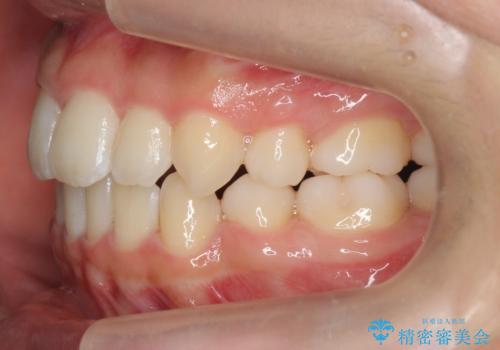

インビザラインチェンジで成功 インビザラインで八重歯の抜歯矯正

- かみ合わせを主訴に来院。

八重歯や、前歯のオープンバイト(開咬)の症状があり、マウスピース(インビザライン)矯正単独では治すのが難しい症状が複合していました。

八重歯や抜歯したスペースの閉鎖をワイヤー矯正で前半行い、治療後半は目立たないインビザラインでかみ合わせを調整しました。

ワイヤー矯正からインビザラインへの変更は、歯磨きも簡単になり、目立たず、さらにワイヤーと併用することで妥協せずしっかり治療結果も出すことができます。